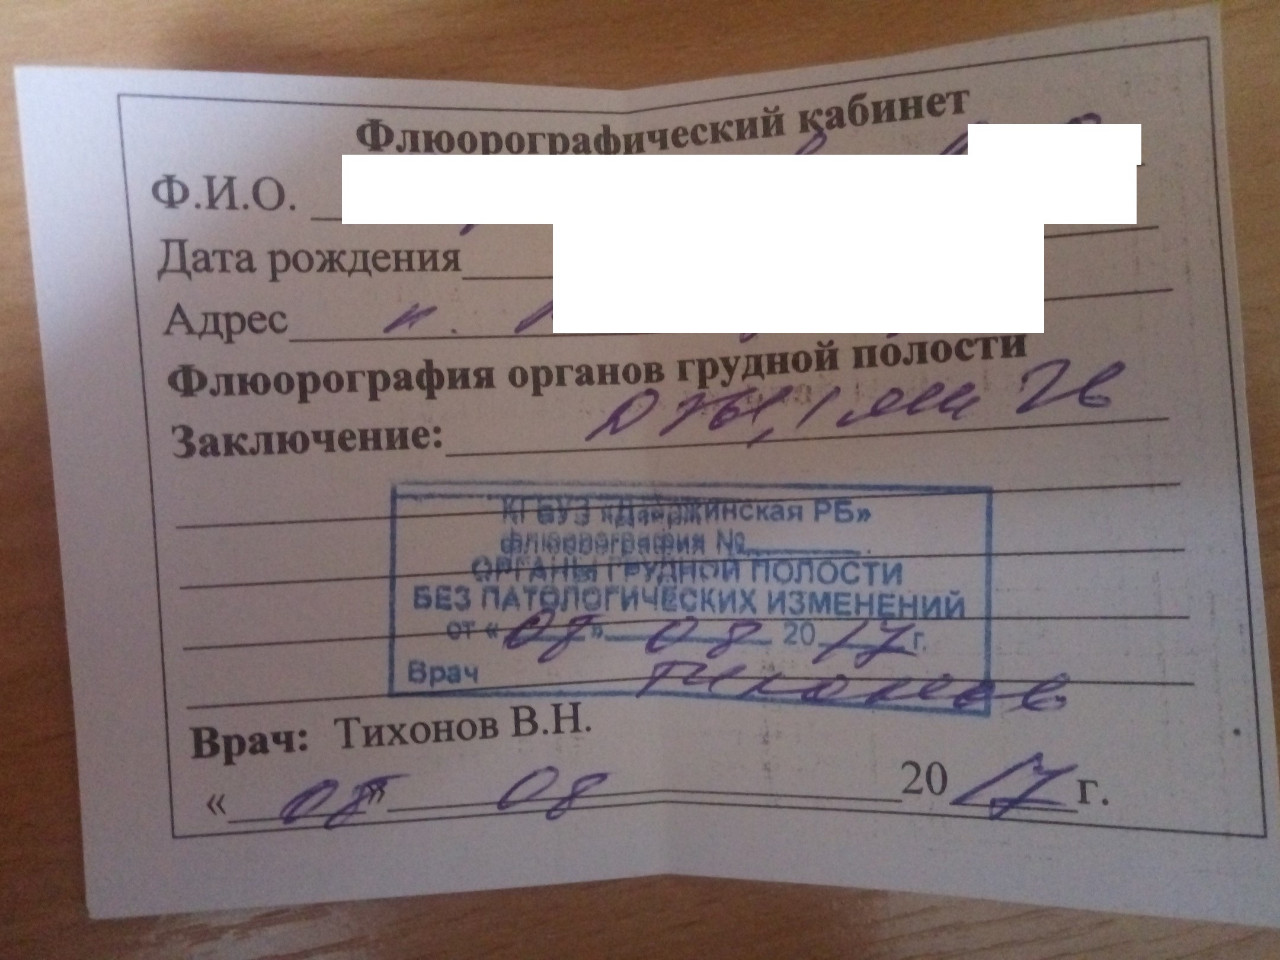

Фотографии рентгеновских снимков без необходимости направления от врача